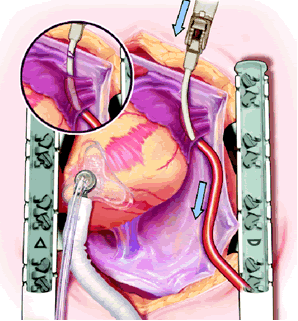

The plane between the LPA and LSPV is developed, and the large bronchus clamp is again passed from cephalad to caudad, with the tip of the clamp being seen caudal to the LIPV. The Robinson catheter is again used to isolate the pulmonary venous drainage on the left side, with the open end of the catheter again being cephalad.

Maintaining the same gentle curve in the clamp, the left-sided pulmonary vein isolation is carried out in a similar fashion to the right side.